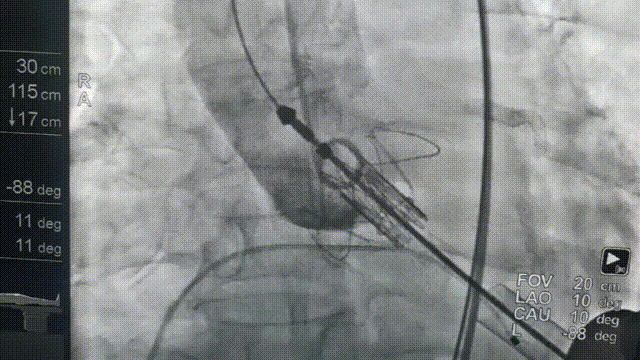

全麻后,首先在心前区的肋间切开3-4CM小切口,暴露心脏的心尖位置,心尖穿刺后进入导丝,利用导丝交换导管鞘完成通路建立。将系统送入左心房,顺利到达二尖瓣病变区域。在经食道超声引导下,术者通过反复评估二尖瓣反流位置、抓捕位置、反流程度,在2区主动脉瓣与二尖瓣闭合线垂直进行巧妙夹合,最终植入一枚ValveClamp®MVC-Ⅲf夹。超声评估夹子固定良好,组织桥完整,无葫芦征,位置、轴向均符合预期。患者术后反流程度从大量转至少量,手术取得圆满成功。患者恢复良好,已经顺利出院。

J-valve瓣膜释放前造影 猪尾导管造影确定瓣环平面

送入16F导管鞘 网状球形跨瓣器,遇腱索缠绕会发生形变